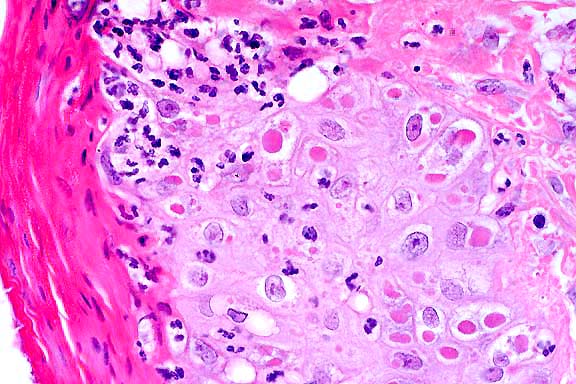

- Case 24-1. Low power view has necrosis and inflammation

of nasal mucosa and thrombosis of nasal vessels. Larger thrombus

demonstrates lines of Zahn (layers of fibrin, wbcs, platelets,

RBCs, etc). Higher power view of vessel wall infiltrated and

replaced by mostly degenerate neutrophils and fibrin. Lines of

Zahn are seen more clearly on the left.